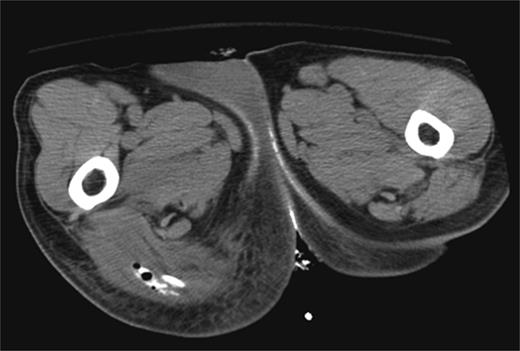

Contrast-enhanced computed tomography (CT) scan revealed the presence of diverticulosis and perirectal mesenteric stranding concerning for diverticulitis (Fig. 1); therefore, the patient was admitted and treated empirically for the same with i.v. antibiotics. He was discharged several days later with a 2-week course of amoxicillin clavulanate.

CT scan depicting perirectal stranding without definite abscess formation.